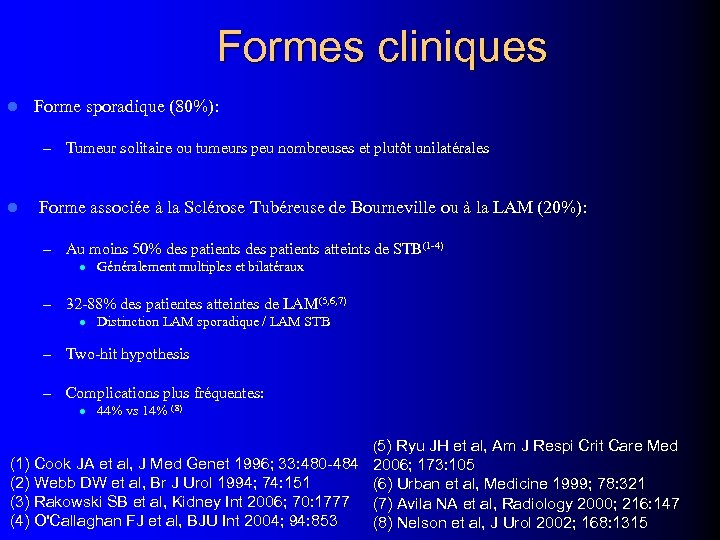

Formes cliniques l Forme sporadique (80%): – l Tumeur solitaire ou tumeurs peu nombreuses et plutôt unilatérales Forme associée à la Sclérose Tubéreuse de Bourneville ou à la LAM (20%): – Au moins 50% des patients atteints de STB(1 -4) l – Généralement multiples et bilatéraux 32 -88% des patientes atteintes de LAM(5, 6, 7) l Distinction LAM sporadique / LAM STB – Two-hit hypothesis – Complications plus fréquentes: l 44% vs 14% (8) (1) Cook JA et al, J Med Genet 1996; 33: 480 -484 (2) Webb DW et al, Br J Urol 1994; 74: 151 (3) Rakowski SB et al, Kidney Int 2006; 70: 1777 (4) O'Callaghan FJ et al, BJU Int 2004; 94: 853 (5) Ryu JH et al, Am J Respi Crit Care Med 2006; 173: 105 (6) Urban et al, Medicine 1999; 78: 321 (7) Avila NA et al, Radiology 2000; 216: 147 (8) Nelson et al, J Urol 2002; 168: 1315

Formes cliniques l Forme sporadique (80%): – l Tumeur solitaire ou tumeurs peu nombreuses et plutôt unilatérales Forme associée à la Sclérose Tubéreuse de Bourneville ou à la LAM (20%): – Au moins 50% des patients atteints de STB(1 -4) l – Généralement multiples et bilatéraux 32 -88% des patientes atteintes de LAM(5, 6, 7) l Distinction LAM sporadique / LAM STB – Two-hit hypothesis – Complications plus fréquentes: l 44% vs 14% (8) (1) Cook JA et al, J Med Genet 1996; 33: 480 -484 (2) Webb DW et al, Br J Urol 1994; 74: 151 (3) Rakowski SB et al, Kidney Int 2006; 70: 1777 (4) O'Callaghan FJ et al, BJU Int 2004; 94: 853 (5) Ryu JH et al, Am J Respi Crit Care Med 2006; 173: 105 (6) Urban et al, Medicine 1999; 78: 321 (7) Avila NA et al, Radiology 2000; 216: 147 (8) Nelson et al, J Urol 2002; 168: 1315